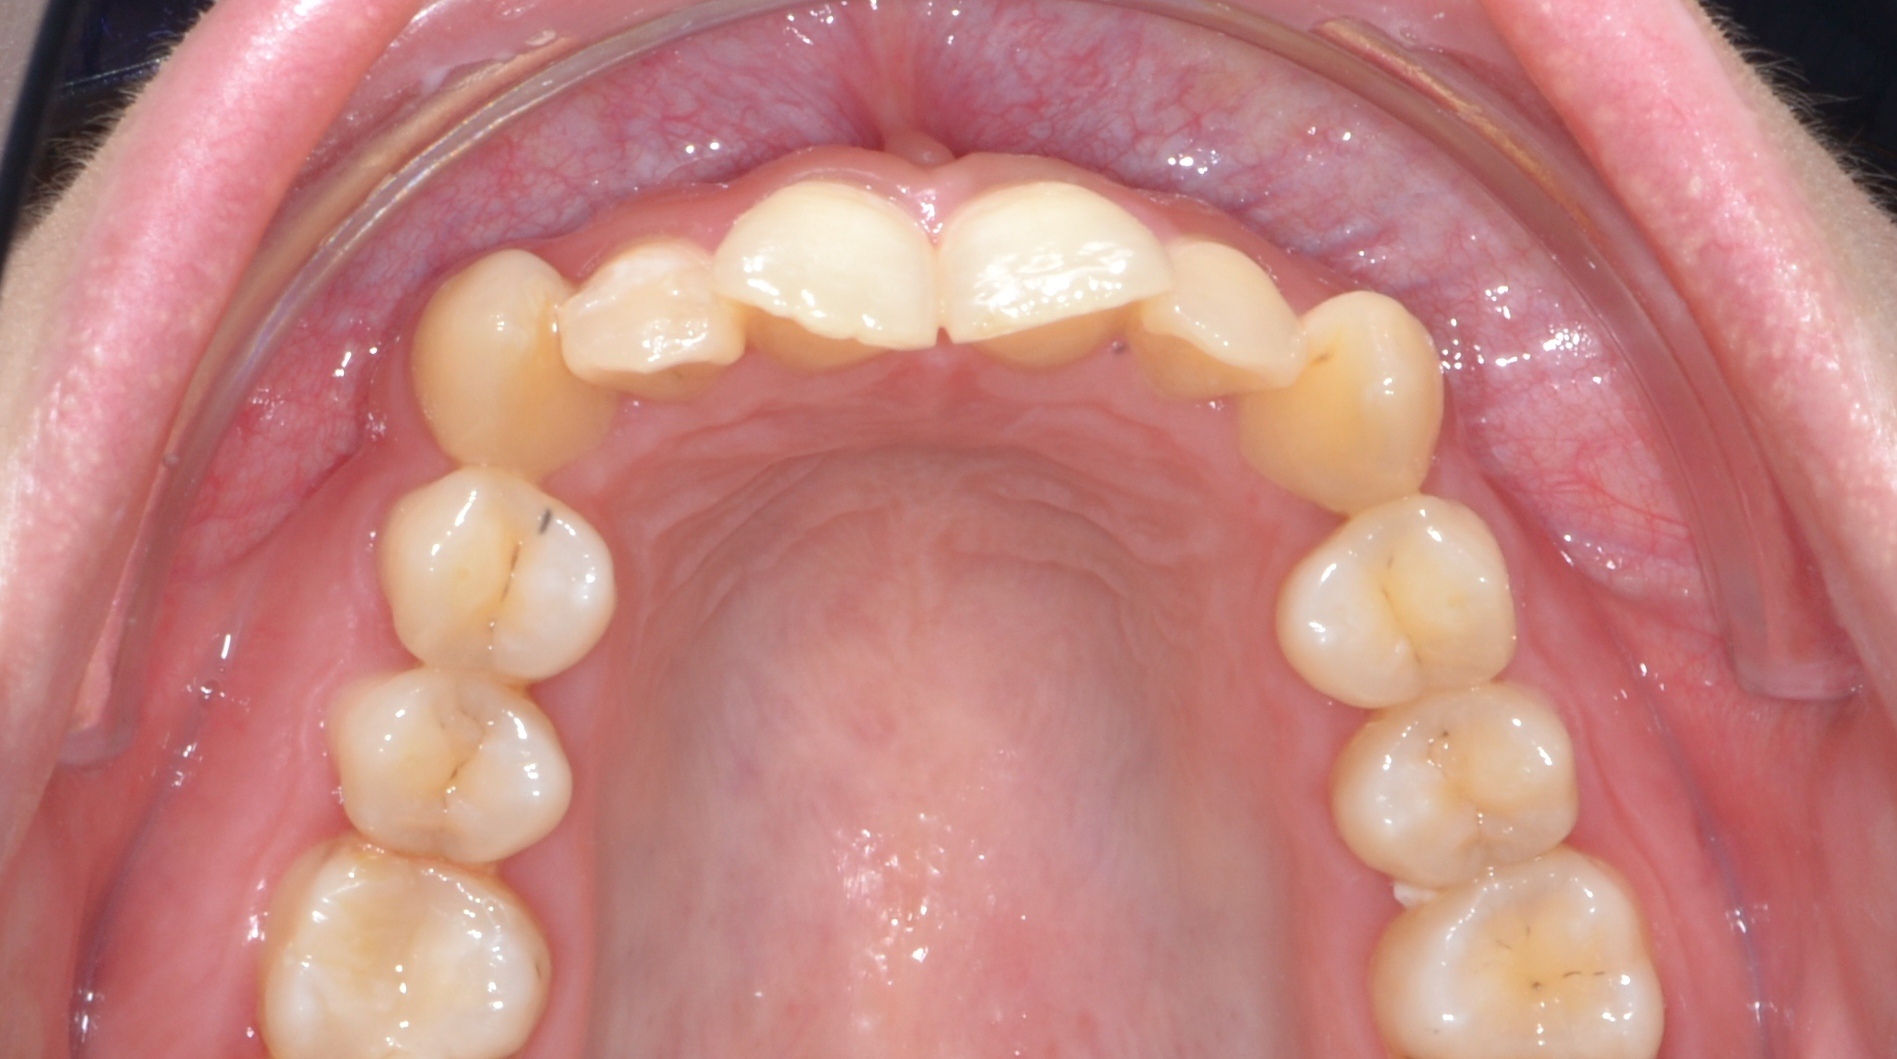

Выявленные проблемы

• Глубокое резцовое перекрытие

• Сужение верхнего и нижнего зубных рядов

• 23 зуб в щёчном положении, 22 зуб в нёбном положении с дефицитом места

• Скученное положение зубов дистальное положение и ротация нижней челюсти

• Патологическая стираемость и генерализованный пародонтит с рецессией десневого края

Брекет-система Q